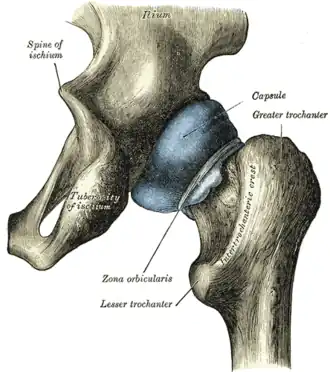

![]() Upper extremity of right femur viewed from behind and above. | |

In human anatomy, the lesser trochanter is a conical, posteromedial, bony projection from the shaft of the femur. It serves as the principal insertion site of the iliopsoas muscle.[1]

The lesser trochanter is a conical posteromedial projection of the shaft of the femur, projecting from the posteroinferior aspect of its junction with the femoral neck.[1]

From its apex three well-marked borders extend:[2]

- two of these are above

- a medial continuous with the lower border of the femur neck

- a lateral with the intertrochanteric crest

- the inferior border is continuous with the middle division of the linea aspera

The summit of the lesser trochanter gives insertion to the tendon of the psoas major muscle and the iliacus muscle;[3] the lesser trochanter represents the principal attachment of the iliopsoas.[1]

The intertrochanteric crest (which demarcates the junction of the femoral shaft and neck posteriorly) extends between the lesser trochanter and the greater trochanter on the posterior surface of the femur.[1]